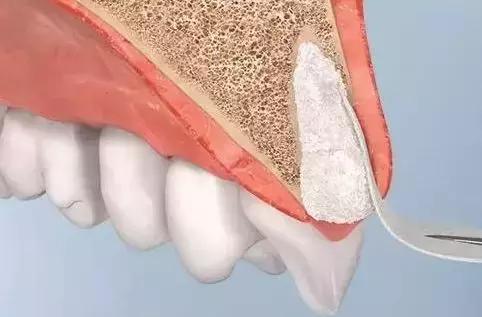

广义的“位点保存”即指拔牙术中或术后为减少牙槽骨吸收,促进牙槽窝内新骨形成所采取的一系列临床治疗方法。

Sclar 于 2004 年首次提出较为规范的拔牙位点保存技术,即在拔牙窝内植入异种骨粉颗粒,表面覆盖可吸收性胶原膜以修复牙槽骨缺损。

GBR(guided bone regeneration引导骨再生技术):将生物膜固定在软组织和骨缺损之间,利用生物膜屏障阻止生长速度更快的上皮细胞和成纤维细胞长入,创造出骨组织优势生长的环境,成骨细胞优先进入骨缺损,无竞争生长。通常还配合骨缺损处的骨移植。

说人话就是:骨头缺损的地方呢就好比空着的“地盘”,牙龈、根周膜和牙槽骨都想占上,但是呢,软组织的细胞跑得快呀,骨组织的细胞跑得慢呀,怎么样能让骨组织给占上呢,招标。用招标的方式——生物膜把软组织隔开,把“地盘”圈起来,让骨细胞慢慢跑,都是骨细胞的。

那么,骨粉起啥作用呢?把骨细胞比作行进缓慢的步兵的话,骨粉好比工兵搭建的桥梁,可以帮助骨细胞跨越较大的缺口,直至抵达胜利的对岸。

生物膜除了能促进骨组织优势形成,还能防止植入物泄漏,协助创口封闭。